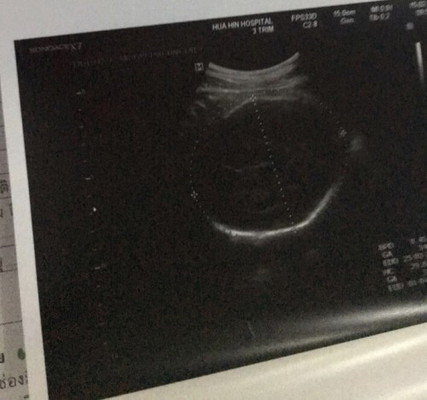

น้องได้33 สัปดาห์ 4วัน น้ำหนัก1,891 g เเล้วค่ะ คุณหมอบอกสมบูรณ์เเข็งเเรงดีค่ะ คุณเเม่ท่านอื่นน้องนํ้าหนักเท่าไหร่เเล้วบ้างค่ะ